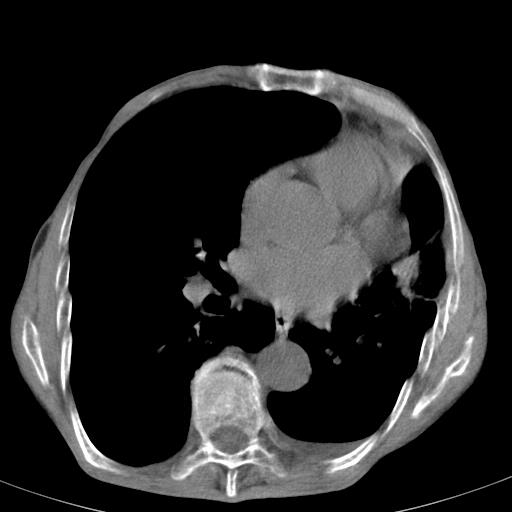

患者78岁,咳嗽胸闷一年余,近月来左侧胸痛;

建议强化,首先考虑左肺癌胸膜转移。

左侧少量胸腔积液,局限胸膜增厚,结合病史,考虑慢性肺炎.

患者左侧胸廓塌陷说明是长期病变,考虑tb性胸膜炎可能性大,另外有明显的肺气肿,建议行结核菌素实验,或者增强扫描

1.慢支肺气肿。2.左肺感染,建议治疗后复查。3.左侧少量胸水。

1.慢支肺气肿。2.左肺感染,建议治疗后复查,待除外继发性肺结核合并感染。3.左侧少量胸水。

1)考虑左肺慢性感染性病变(结核可能)。2)左肺上叶周围型肺癌不排除;建议追踪复查。3)肺气肿。4)左侧胸腔积液,左侧胸膜增厚、粘连。

1)考虑左肺慢性感染性病变(结核可能)。2)肺气肿。4)左侧胸腔积液,左侧胸膜增厚、粘连。3)左肺上叶周围型肺癌不排除;建议追踪复查。